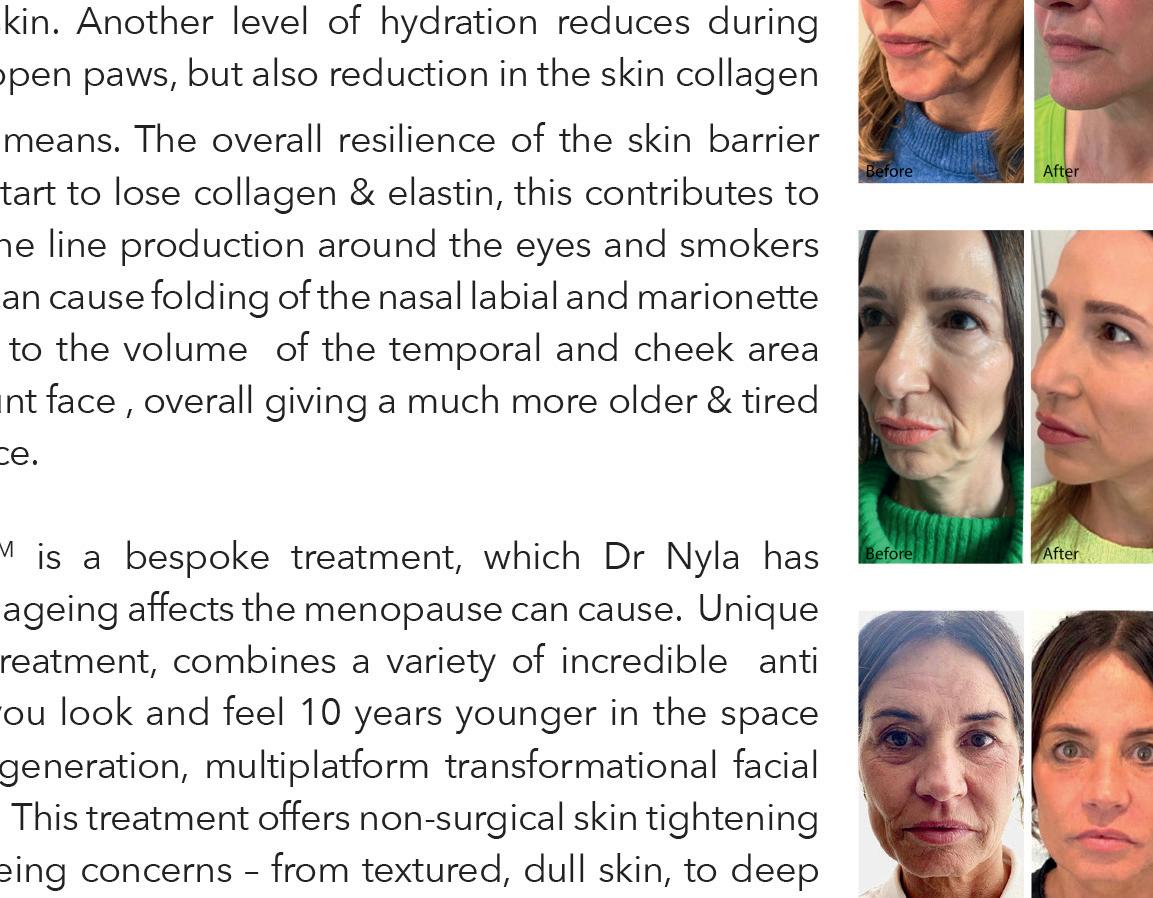

The Transformation FaceliftTM is a bespoke treatment, which Dr Nyla has designed to treat many of the ageing affects the menopause can cause. Unique to the medispa group, this treatment, combines a variety of incredible anti ageing treatments to make you look and feel 10 years younger in the space of only six weeks! The next generation, multiplatform transformational facial offered exclusively at Dr Nyla. This treatment offers non-surgical skin tightening and lifting to treat all anti-ageing concerns –from textured, dull skin, to deep wrinkles and loss of laxity.

The Transformation FaceliftTM is a bespoke treatment, which Dr Nyla has designed to treat many of the ageing affects the menopause can cause. Unique to the medispa group, this treatment, combines a variety of incredible anti ageing treatments to make you look and feel 10 years younger in the space of only six weeks! The next generation, multiplatform transformational facial offered exclusively at Dr Nyla. This treatment offers non-surgical skin tightening and lifting to treat all anti-ageing concerns –from textured, dull skin, to deep wrinkles and loss of laxity.

During menopause, lower levels of estrogen have a big impact on your skin. Less estrogen makes you prone to thinning, sagging, and wrinkling. Skin looses elasticity making open pores much more visible. Skin is also much less hydrated. Fortunately, you can relieve some of the skin-related effects of aging by taking care of your specific skin care needs using the Dr Nyla skincare collection.

During menopause, lower levels of estrogen have a big impact on your skin. Less estrogen makes you prone to thinning, sagging, and wrinkling. Skin looses elasticity making open pores much more visible. Skin is also much less hydrated. Fortunately, you can relieve some of the skin-related effects of aging by taking care of your specific skin care needs using the Dr Nyla skincare collection.